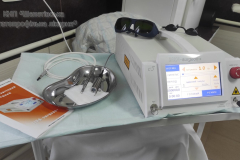

За кошти Шепетівської міської ради у КНП «Шепетівська багатопрофільна лікарня» закуплено лазер хірургічний діодний Lika-Surgeon+.

Даний лазер дає можливість видалити такі передпухлинні стани шкіри як:

– Папіломи

– Кератоми

– Дерматофіброми

– Новуси

– Бородавки

– Шкірний ріг

– Трофічні виразки шкіри

та лікувати базальноклітинний рак шкіри (початкові стадії).

Переваги застосування лазеру хірургічного діодного Lika-Surgeon+:

– Малотравматичність – точний, строго дозований вплив лазерного випромінювання забезпечує мінімальне пошкодження навколишніх тканин.

– Надійний гемостаз – за рахунок коагуляції крові на стінках розрізу лазерні операції практично безкровні, що забезпечує чудовий огляд операційного поля.

– Прецизійність – висока точність лазерного впливу дозволяє контролювати зону пошкодження.

– Стерильність післяопераційної рани – лазерне випромінювання вбиває патогенні мікроорганізми, попереджаючи цим розвиток гнійних ускладнень.

– Безболісність – лазерні операції менш болючі для пацієнта, ніж традиційні втручання; іноді анестезія не потрібна або достатньо лише аплікаційної анестезії.

– У комплектації лазерного коагулятора “Ліка-хірург” (Lika-Surgeon+) входить насадки як для контактного видалення новоутворень так і для безконтактного.

– Видалення новоутворень шкіри проводиться у хірургічному кабінеті консультативно-діагностичної поліклініки Шепетівської багатопрофільної лікарні амбулаторно.